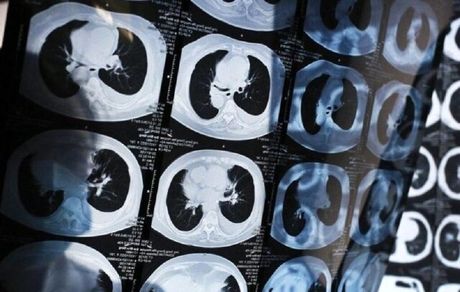

دانشمندان دانشگاه پکن ابزاری مبتنی بر هوش مصنوعی برای تشخیص سرطان ریه در مراحل اولیه توسعه دادند.